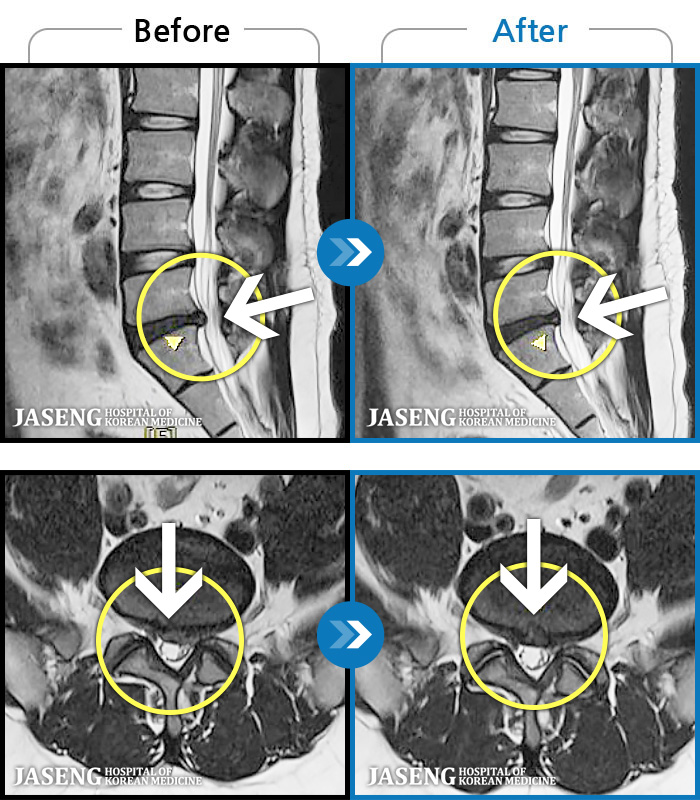

MRI ġ

1,304 MRI ũ ʸ Ȯϼ.